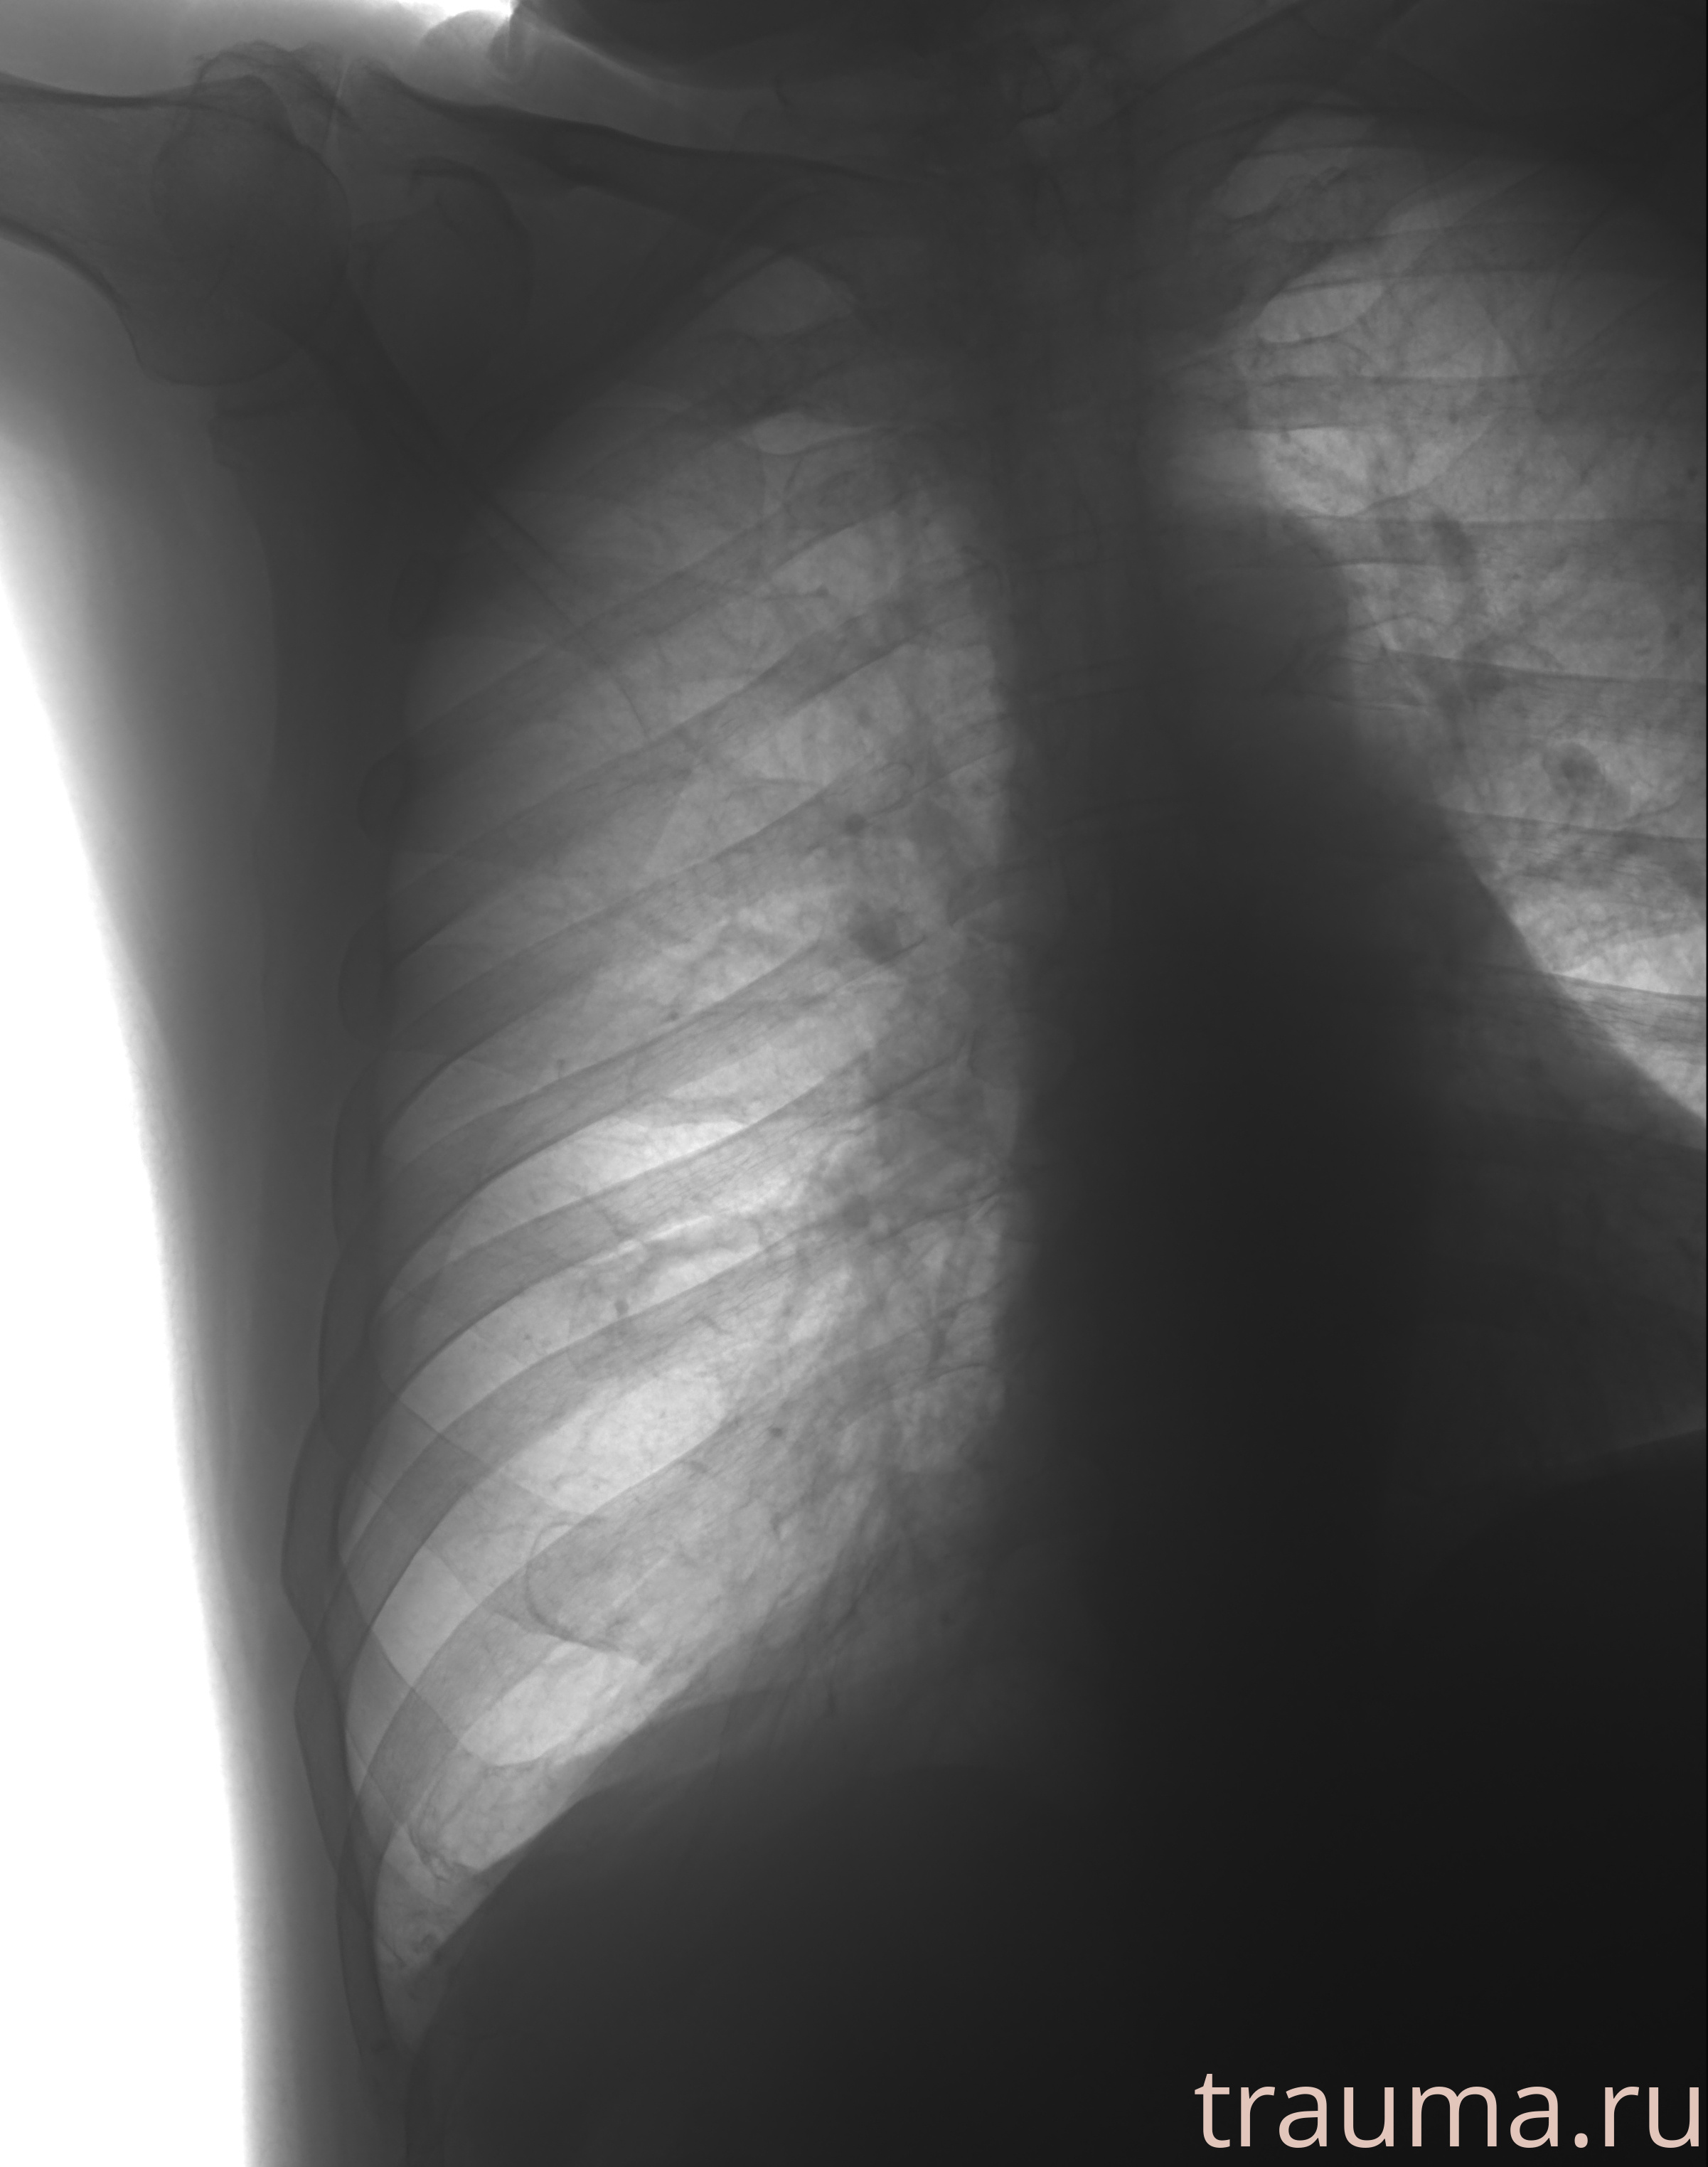

Рентгенограммы

Рентген на дому: по вашему адресу приезжает врач-рентгенолог, травматолог-ортопед с мобильным рентгеновским аппаратом, проводит диагностику травмы или заболевания, делает необходимые рентгенограммы, дает рекомендации по дальнейшему лечению. Получить качественные снимки в домашних условиях возможно благодаря уникальной методике, разработанной МосРентген Центром для института  Склифосовского

Яркость: 1   Контраст: 1   Инвертировать: 0 Увеличение: 1

Перетаскивайте мышь вверх/вниз для контраста, влево/право для яркости. Прокрутка колесом изменяет масштаб. Нажмите Сбросить для возврата к исходному изображению. При увеличении держите мышь в той области, которую хотите рассмотреть.